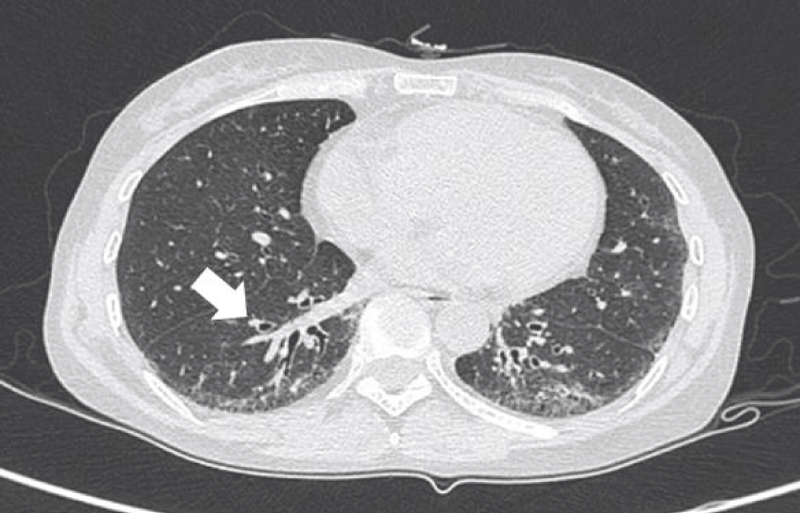

HRCT images

The most common presentation on HRCT were ground-glass opacities, showed 79.3% (92 patients). Secondly, 74.1% patients showed interlobular septal thickening, followed by reticular opacities(58.6%), intralobular interstitial thickening(45.7%), mediastinal lymph node enlargement(36.2%), nodules(30.2%), honeycomb cysts (29.3%), traction bronchiectasis(21.6%), stripes(17.2%), pleural thickening(14.7%), pleural effusion(10.3%), dilation of the esophagus(6.9%), emphysema(6.9%), bullae(5.2%), consolidation(5.2%), subpleural line(0.9%) (Figures 1-9).

Figure 5: Traction bronchiectasis.

Inflammatory cell infiltration in lung tissue, lymphedema and fibrous tissue hyperplasia pulled bronchus and bronchioles resulting in irregular bronchiectasis. Traction bronchiectasis were showed thickening of the wall, expansion the lumen as dual track or irregular bag-like changes [6].